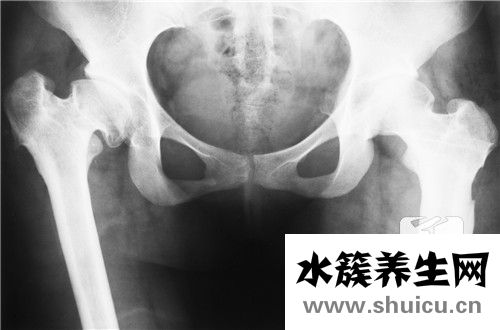

1.X線檢查

在X線x光片上由此可見挨近關節面處的髂骨皮層出現壞死性改變,骨質增生呈高密度狀,坐落于骶髂關節下1/2處,且多呈三角形;骶髂關節空隙齊整、清楚,關節面及骨質增生無毀壞征。以一側多見,亦有雙側者。